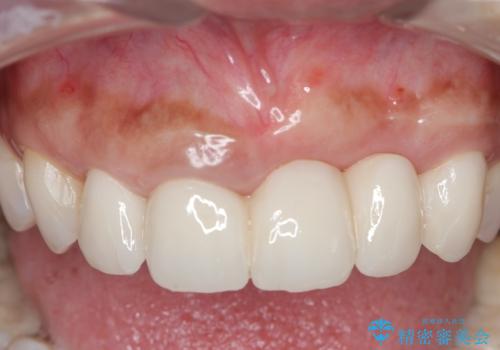

歯槽堤保存術を併用したブリッジ治療

- 前歯がグラグラし、においもする、とのことで改善を求めて来院されました。

一見して問題ないように見える左側の2前歯は、セラミックを除去してみると亀裂や虫歯の再発が見られました。

抜歯時に可及的に歯肉のボリュームを保つよう骨充填材とコラーゲン製剤による填塞を行い審美的かつ機能的なブリッジとなるよう治療を進めます。

- 66万円(ジルコニアクラウン×5・仮歯×5)費用は治療当時の料金となります

一件綺麗に見えるセラミックも適合や精度が悪いと、内部で虫歯が進行し亀裂や破折、悪臭の原因となることがあります。